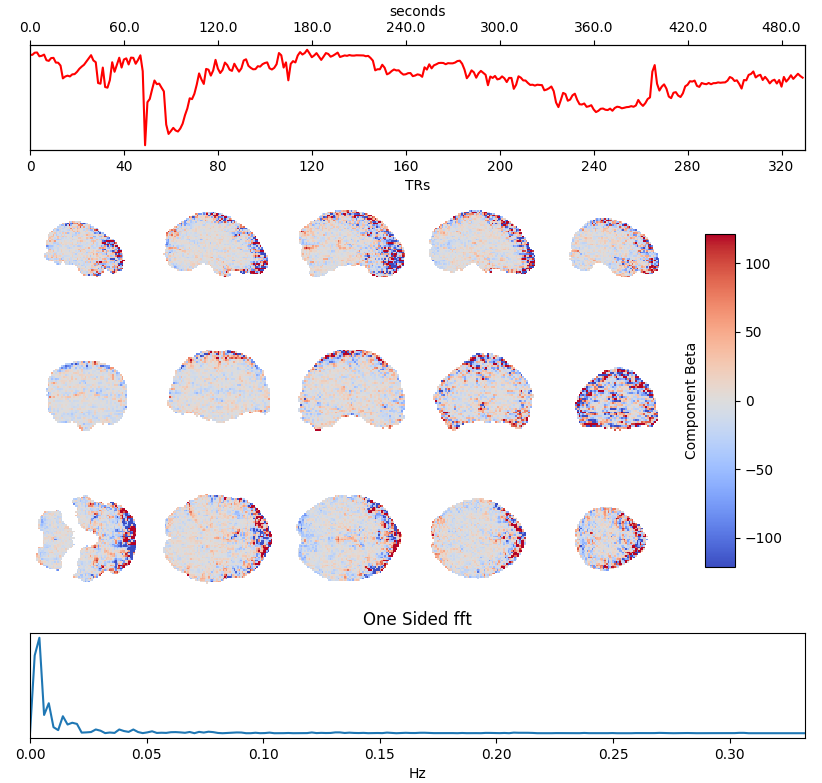

ICA denoising

Independent Component Analysis (ICA) is commonly used to remove motion effects and other sources of noise from fMRI data

Motion

Motion + MB artefact

CSF pulsations

Griffanti et al. 2014 (NeuroImage), 2017 (NeuroImage), The tedana Community et al. 2021 (Zenodo)

Which ICA denoising?

What is the best way to denoise BH data after ICA?

being too aggressive might remove the signal of interest,

but being too conservative might keep too much noise in the model.

Methods: ME-ICA based denoise

What is the best way to denoise BH data after ICA?

being too aggressive might remove the signal of interest,

but being too conservative might keep too much noise in the model.

- Aggressive model: nuisance regression using only noise ICA-components (ME-AGG): $$ Y_{OC} = P_{ET}CO_2{hrf} + Mot + Poly + [IC_{rej} \perp (Mot,Poly) ] + n $$

- Moderate model: noise components are orthogonalised w.r.t. the CO2 trace (ME-MOD): $$ Y_{OC} = P_{ET}CO_2{hrf} + Mot + Poly + [IC_{rej} \perp (P_{ET}CO_2{hrf},Mot,Poly) ] + n $$

- Conservative model: noise components are orthogonalised w.r.t. the CO2 trace and the other components (ME-CON): $$ Y_{OC} = P_{ET}CO_2{hrf} + Mot + Poly + [IC_{rej} \perp (P_{ET}CO_2{hrf},IC_{acc},Mot,Poly) ] + n $$

- Optimal combination only (OC-MPR): $$ Y_{OC} = P_{ET}CO_2{hrf} + Mot + Poly + n $$

- Single echo only (second echo used as proxy, SE-MPR): $$ Y_{SE} = P_{ET}CO_2{hrf} + Mot + Poly + n $$

We set up a simultaneous estimation and denoise step, considering motion parameters,

their derivative, Legendre polynomials to the fourth order, and:

- Aggressive model: nuisance regression using only noise ICA-components (ME-AGG): $$ Y_{OC} = P_{ET}CO_2{hrf} + Mot + Poly + [IC_{rej} \perp (Mot,Poly) ] + n $$

- Moderate model: noise components are orthogonalised w.r.t. the CO2 trace (ME-MOD): $$ Y_{OC} = P_{ET}CO_2{hrf} + Mot + Poly + [IC_{rej} \perp (P_{ET}CO_2{hrf},Mot,Poly) ] + n $$

- Conservative model: noise components are orthogonalised w.r.t. the CO2 trace and the other components (ME-CON): $$ Y_{OC} = P_{ET}CO_2{hrf} + Mot + Poly + [IC_{rej} \perp (P_{ET}CO_2{hrf},IC_{acc},Mot,Poly) ] + n $$

- Optimal combination only (OC-MPR): $$ Y_{OC} = P_{ET}CO_2{hrf} + Mot + Poly + n $$

- Single echo only (second echo used as proxy, SE-MPR): $$ Y_{SE} = P_{ET}CO_2{hrf} + Mot + Poly + n $$

Alternative ICA based denoise (sequential)

What is the best way to denoise the data after ICA?

Regression based:

Aggressive approach: nuisance regression using only the rejected components.

Non aggressive (partial regression) approach: all the components are considered, but only the rejected components are regressed out of the data.

Orthogonalised approach: the rejected components are orthogonalised with respect to the other components.

4D-based approach (similar to M/EEG): reconstruct volumes on noise, then subtract it from the original data.